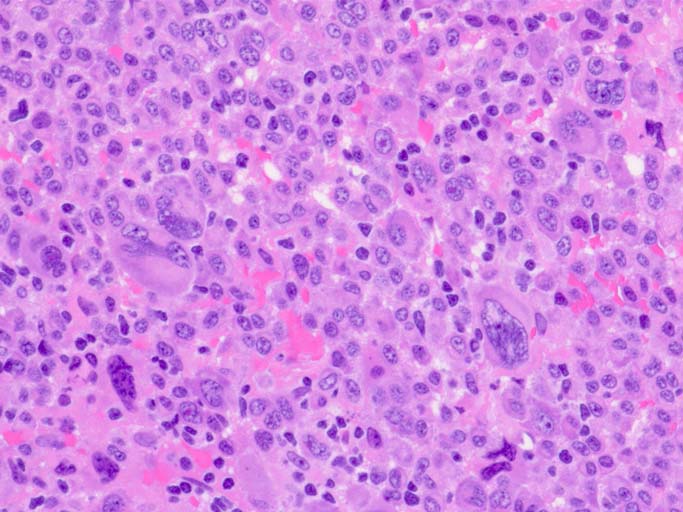

normal plasma cell, myeloma cell, plasmacytoma(bone)の細胞組織像

(サムネイル画像のクリックで大きな画像が見られます) 1-3はASD-Giemsa染色. 4はHE.